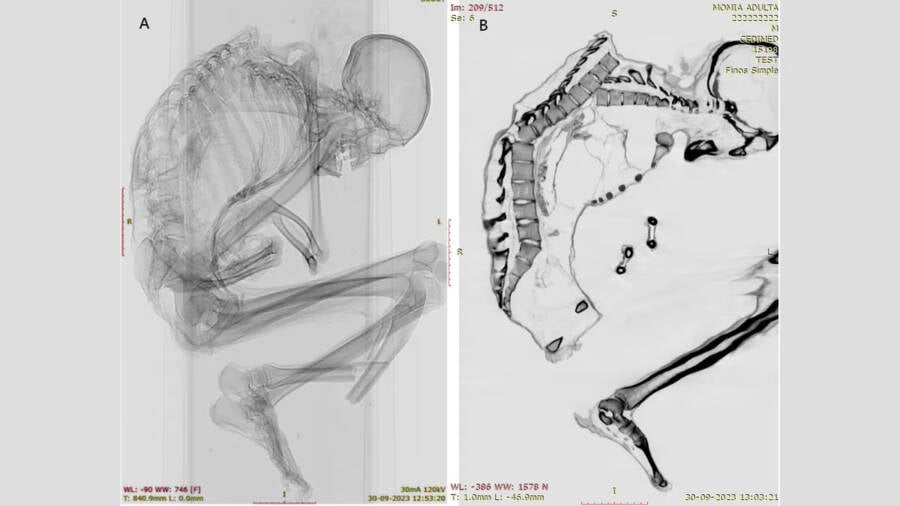

Francisco Garrido and Catalina MoralesX-rays and CT scans of the mummified man revealed the extent of his injuries.

CT scans and X-ray imagery showed signs of blunt force trauma on the man’s skeleton, suggesting he died because of a rockfall or mine collapse. These findings, published recently in the International Journal of Osteoarchaeology, are providing new insight into the history of turquoise mining in Chile.

Researchers led by archaeologists Francisco Garrido and Catalina Morales of the National Museum of Natural History in Santiago utilized CT scans and X-ray imagery to examine the internal injuries of the mummy. The results painted a grim picture of a mining disaster.

“We found extensive injuries to the man’s back, ribs, collarbone, shoulder blades and lower limb bones,” the researchers wrote in the study. “Considering the archaeological context, this individual likely died while extracting turquoise, when a rock fell on his back from the ceiling of the mine.”

The lack of healing on the bone fractures confirmed that all injuries occurred immediately prior to death.